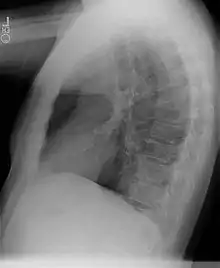

Diagnostic

Le diagnostic se fait le plus souvent dans la petite enfance, pendant les six premiers mois de vie[3], mais peut aussi être réalisé à l'âge adulte[2]. Les séquestrations extra-lobaires peuvent par ailleurs être dépistées in utero par échographie[3].

La tomodensitométrie thoracique, avec injection de produit de contraste iodé, permet généralement d'évoquer le diagnostic.